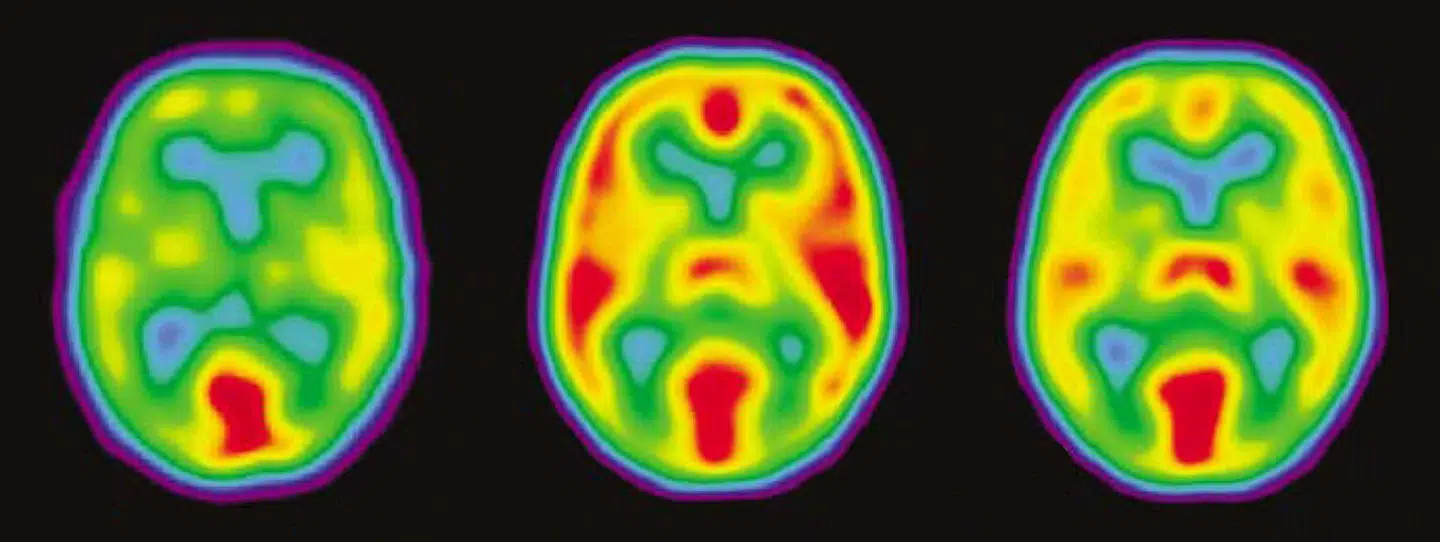

Med den særlige positron-emissionstomografiske (PET) metode kan man måle værdier for ilt- og druesukkerforbrug i hjernen, hvilket alle anerkender som de vigtigste deltagere i nedbrydningen af næringsstoffer i hjernen og derfor som en betingelse for hjernens arbejde i vågen (eller sovende) tilstand.

PET blev derfor et vigtigt værktøj, da det lykkedes forskere at måle forbrændingen af druesukker direkte i små områder i menneskehjernen. Kortlægningen af hjernens energiomsætning med radioaktivt mærket druesukker var opfundet af Louis Sokoloff ved NIH i Bethesda i 1974 og sat i værk af Abass Alavi i Philadelphia i 1976. Metoden blev indført i Danmark i 1989 af Olaf Paulson i København og i 1993 af Søren Hansen og undertegnede i Aarhus, da jeg kom fra Canada.